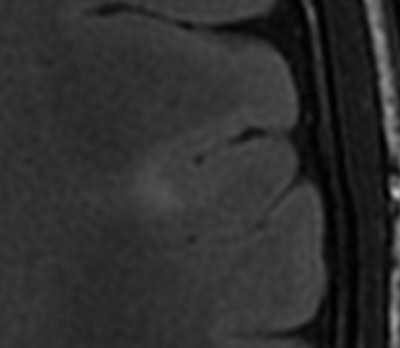

"The signal doesn't need to be abnormal," Ertl-Wagner explained. "With polymicrogyria, for example, where there are too many too small gyri, you usually have a normal signal but an abnormal gray matter-white matter junction."

The root cause of epilepsy can be very challenging to diagnose as often the abnormalities causing it can be very small, according to Ertl-Wagner. Some of the tiny focal cortical dysplasias with very small signal abnormalities are hard to visualize, and hard to pick up in images of the entire brain, she added.

Here diagnosis requires high resolution, preferably with a very good 3-tesla MR scanner, and optimized sequences, including 3D sequences, such as 3D FLAIR and 3D T1, and then for radiologists to really look for the focus, because finding it or not carries important therapeutic consequences for the patient.

"Do we find a dysplasia? Do we find a polymicrogyria? Do we find only one or more than one? This influences the therapeutic approach -- for example, whether the focus can be resected or not. If you oversimplify your approach you are going to miss abnormalities and send the patient down the wrong path," she said.